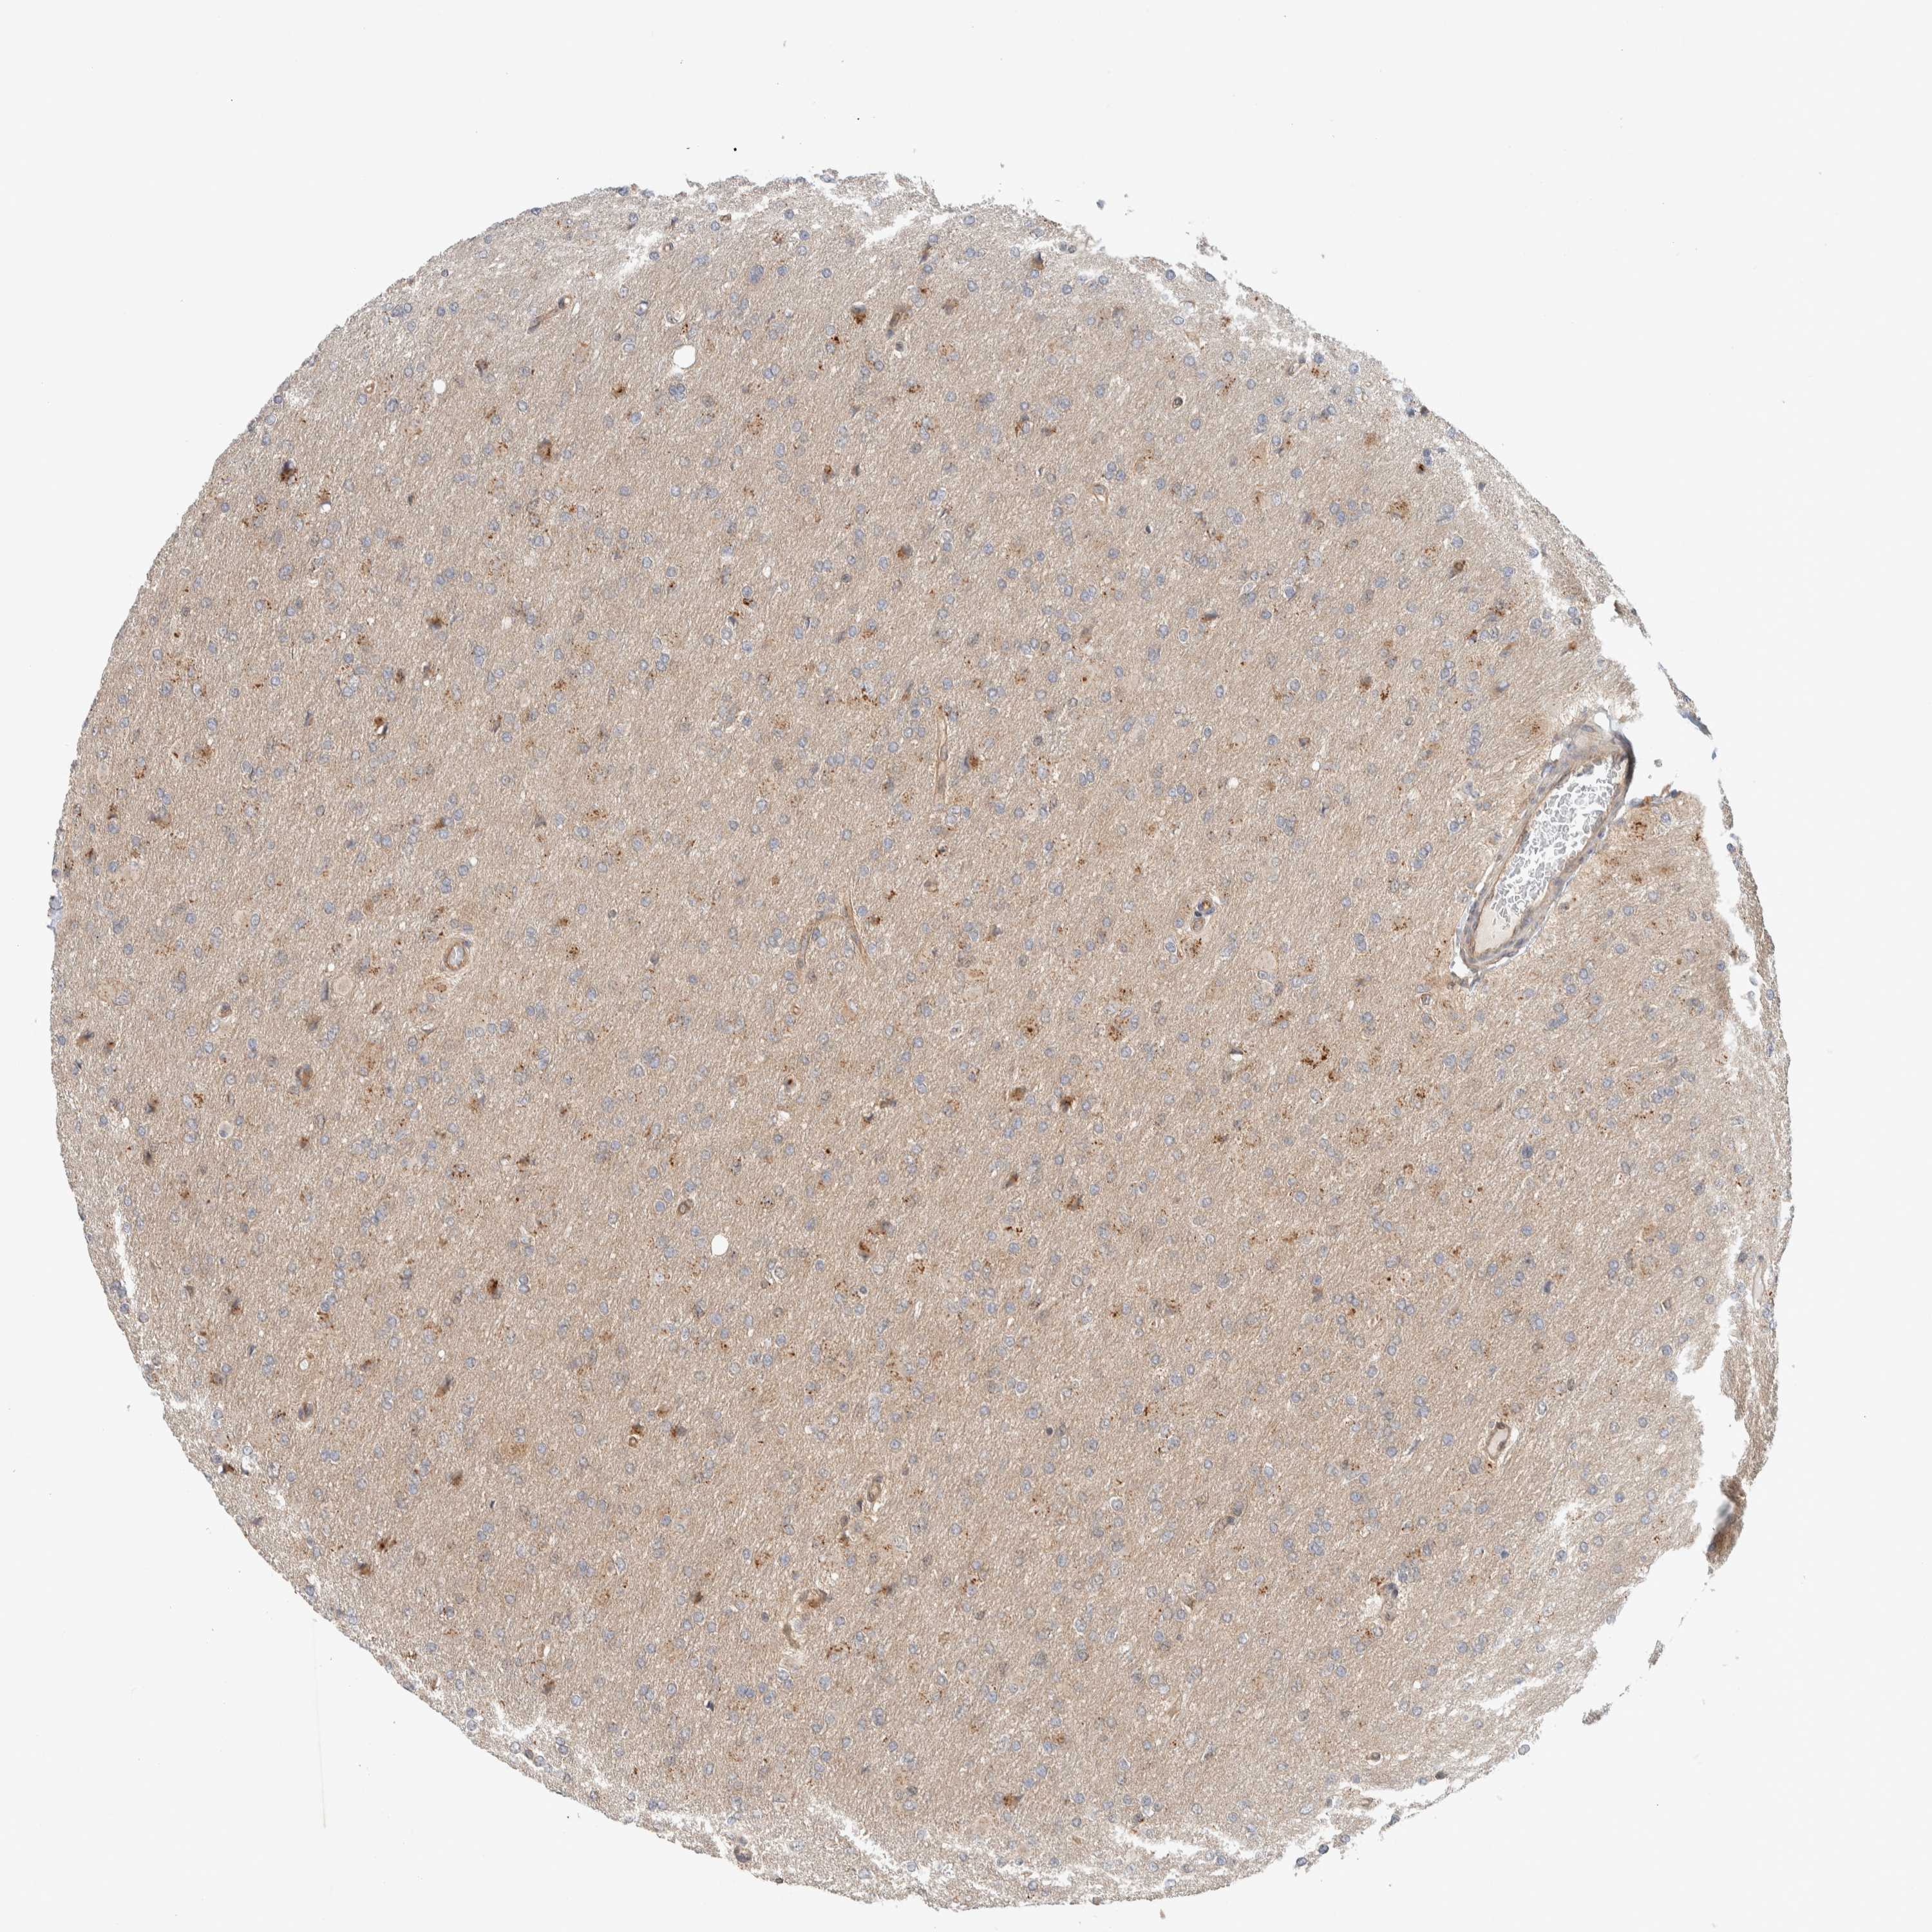

GLIOMA - Protein expressioni

A mouse-over function shows sample information and annotation data. Click on an image to view it in a full screen mode. Samples can be filtered based on level of antibody staining by selecting one or several of the following categories: high, medium, low and not detected. The assay and annotation is described here.

Note that samples used for immunohistochemistry by the Human Protein Atlas do not correspond to samples in the TCGA dataset.

Antibody stainingi

Antibody staining in the annotated cell types in the current human tissue is reported as not detected, low, medium, or high, based on conventional immunohistochemistry profiling in selected tissues. This score is based on the combination of the staining intensity and fraction of stained cells.

Each image is clickable and will lead to virtual microscopy that enables deeper exploration of all samples and also displays staining intensity scores, fraction scores and subcellular localization as well as patient and tissue information for each sample.

Antibody HPA023938

Antibody HPA023945

Antibody HPA024011

Antibody CAB020841

Staining

High

Medium

Low

Not detected

Intensity

Strong

Moderate

Weak

Negative

Quantity

>75%

75%-25%

<25%

None

Location

Nuclear

Cytoplasmic/membranous

Cytoplasmic/membranous,nuclear

Glioma, malignant, High grade

Glioma, malignant, Low grade